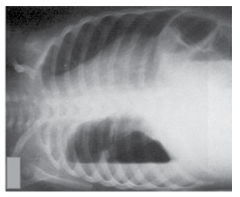

A imagem a seguir representa qual exame do tórax?